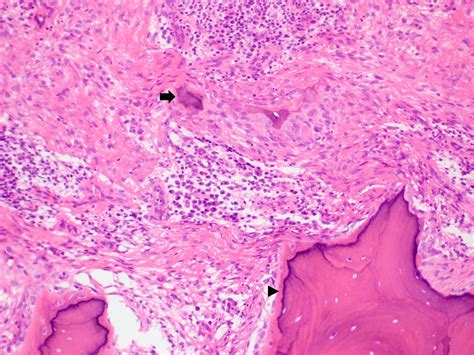

In most cases, a clinical diagnosis is sufficient. However, if the lesion appears atypical, grows rapidly, or has an unusual appearance, the dentist may recommend an excisional biopsy. This is a simple procedure where the tissue is removed and sent to a laboratory to be examined under a microscope by a pathologist. This is a standard precautionary measure to ensure the lesion is indeed benign.

• oral fibroma pathology outlines